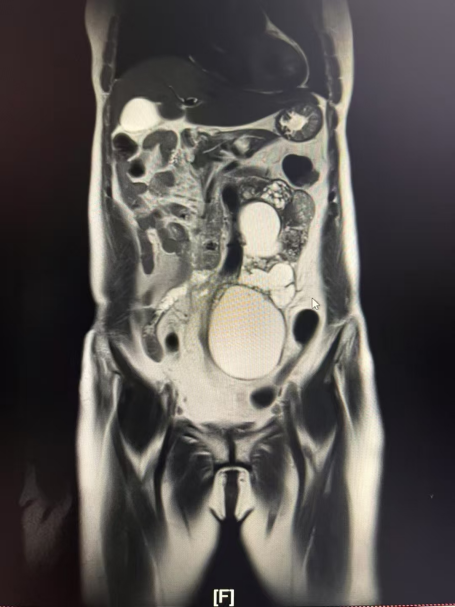

灣區(qū)時(shí)訊(編輯/劉秀 通訊員/文朝陽(yáng) 陳鋆 鄭敏珊 )“就像千萬(wàn)顆珠子被無(wú)形的力量擠壓在一起,形成了堅(jiān)硬的石塊。”60歲的厚阿姨(化名)來(lái)自甘肅省定西市,先天性單側(cè)耳聾、失明的她,一生坎坷卻堅(jiān)韌。然而近半年來(lái),持續(xù)加重的腹脹、腹痛將她推向新的絕境。輾轉(zhuǎn)多家醫(yī)院后,她被確診為罕見(jiàn)的卵巢顆粒細(xì)胞瘤腹膜后復(fù)發(fā),腫瘤直徑超過(guò)20cm,像一條串珠般緊緊附著在腹腔的大血管上,不斷攫取著營(yíng)養(yǎng)。

就在厚阿姨一家?guī)缀醴艞墪r(shí),親友推薦她前往中腫甘肅醫(yī)院一試。今年3月,中山大學(xué)腫瘤防治中心婦科熊櫻主任醫(yī)師作為第七批專家進(jìn)駐中腫甘肅醫(yī)院,擔(dān)任中腫甘肅醫(yī)院婦瘤科執(zhí)行主任。接診厚阿姨后,熊櫻主任沒(méi)有輕易否定手術(shù)可能。他帶領(lǐng)婦瘤二科成員仔細(xì)研究病史及影像資料,發(fā)現(xiàn)腫瘤雖然體積巨大,并擠壓腹腔段的主動(dòng)脈及左腎血管,導(dǎo)致血管明顯移位,但尚未完全包裹血管,而且患者無(wú)局部放療史及反復(fù)手術(shù)史。熊櫻主任立即組織多學(xué)科會(huì)診,制定詳細(xì)的手術(shù)預(yù)案。

手術(shù)當(dāng)日,熊櫻主任主刀,婦瘤二科青年醫(yī)護(hù)團(tuán)隊(duì)通力配合。無(wú)影燈下,腹腔打開(kāi)后,20多公分串珠狀的腫瘤赫然可見(jiàn),將降結(jié)腸、乙狀結(jié)腸系膜高高頂起。熊櫻主任手持手術(shù)電刀,小心翼翼將被覆在腫瘤表面的腸系膜完整游離,保護(hù)了大腸的血供。隨后將腸管及系膜完全翻起,顯露腹膜后的腫瘤。這時(shí)發(fā)現(xiàn)腫瘤緊貼在腹主動(dòng)脈的左側(cè)壁,腫瘤底部已侵犯椎前筋膜和腰大肌,向下延伸至骶岬前及直腸后間隙,向上延伸生長(zhǎng)至左腎血管背側(cè),腫瘤最上級(jí)已超過(guò)腎血管上緣。憑借多年在“血管表面舞蹈”積累下來(lái)的豐富經(jīng)驗(yàn)和精湛技藝,熊櫻主任手中的手術(shù)刀在血管與腫瘤的縫隙間精準(zhǔn)游走,每一步分離都如庖丁解牛,既嚴(yán)格控制了出血,又保證了腫瘤的完整切除。最后在切除左腎血管背側(cè)的腫瘤時(shí),熊櫻主任將左腎完全游離,并將腎臟及血管翻起至對(duì)側(cè),這一“腎反轉(zhuǎn)”的神操作全面暴露腫瘤并完成徹底的切除!